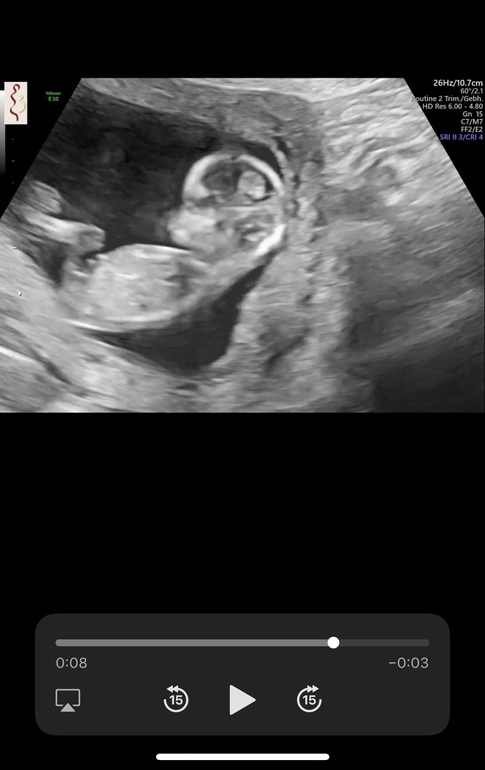

Если то что я вижу на последнем снимке это половой бугорок, то это мальчик, ну и по форме головы тоже можно предположить мальчика 🤗

Катя, мне кажется половой бугорок тут между ножек, серого цвета) белым на узи кости подсвечиваются) я очень сильно чувствую девочку, думала все предположения тоже о девочке будут 😄

Как раз угол что вы нарисовали девчачий. Такчто мой вердикт "диванного эксперта"- девочка). Автору удачи и главное здорового малыша.

Я коряво нарисовала, у меня тоже узи было 12+2 и пиптик под оооочень похожим наклоном... 😉 так что я всеже за мальчика🙃

Вот тоже узи 12+2 и кстати мне тоже писали все что девочка...